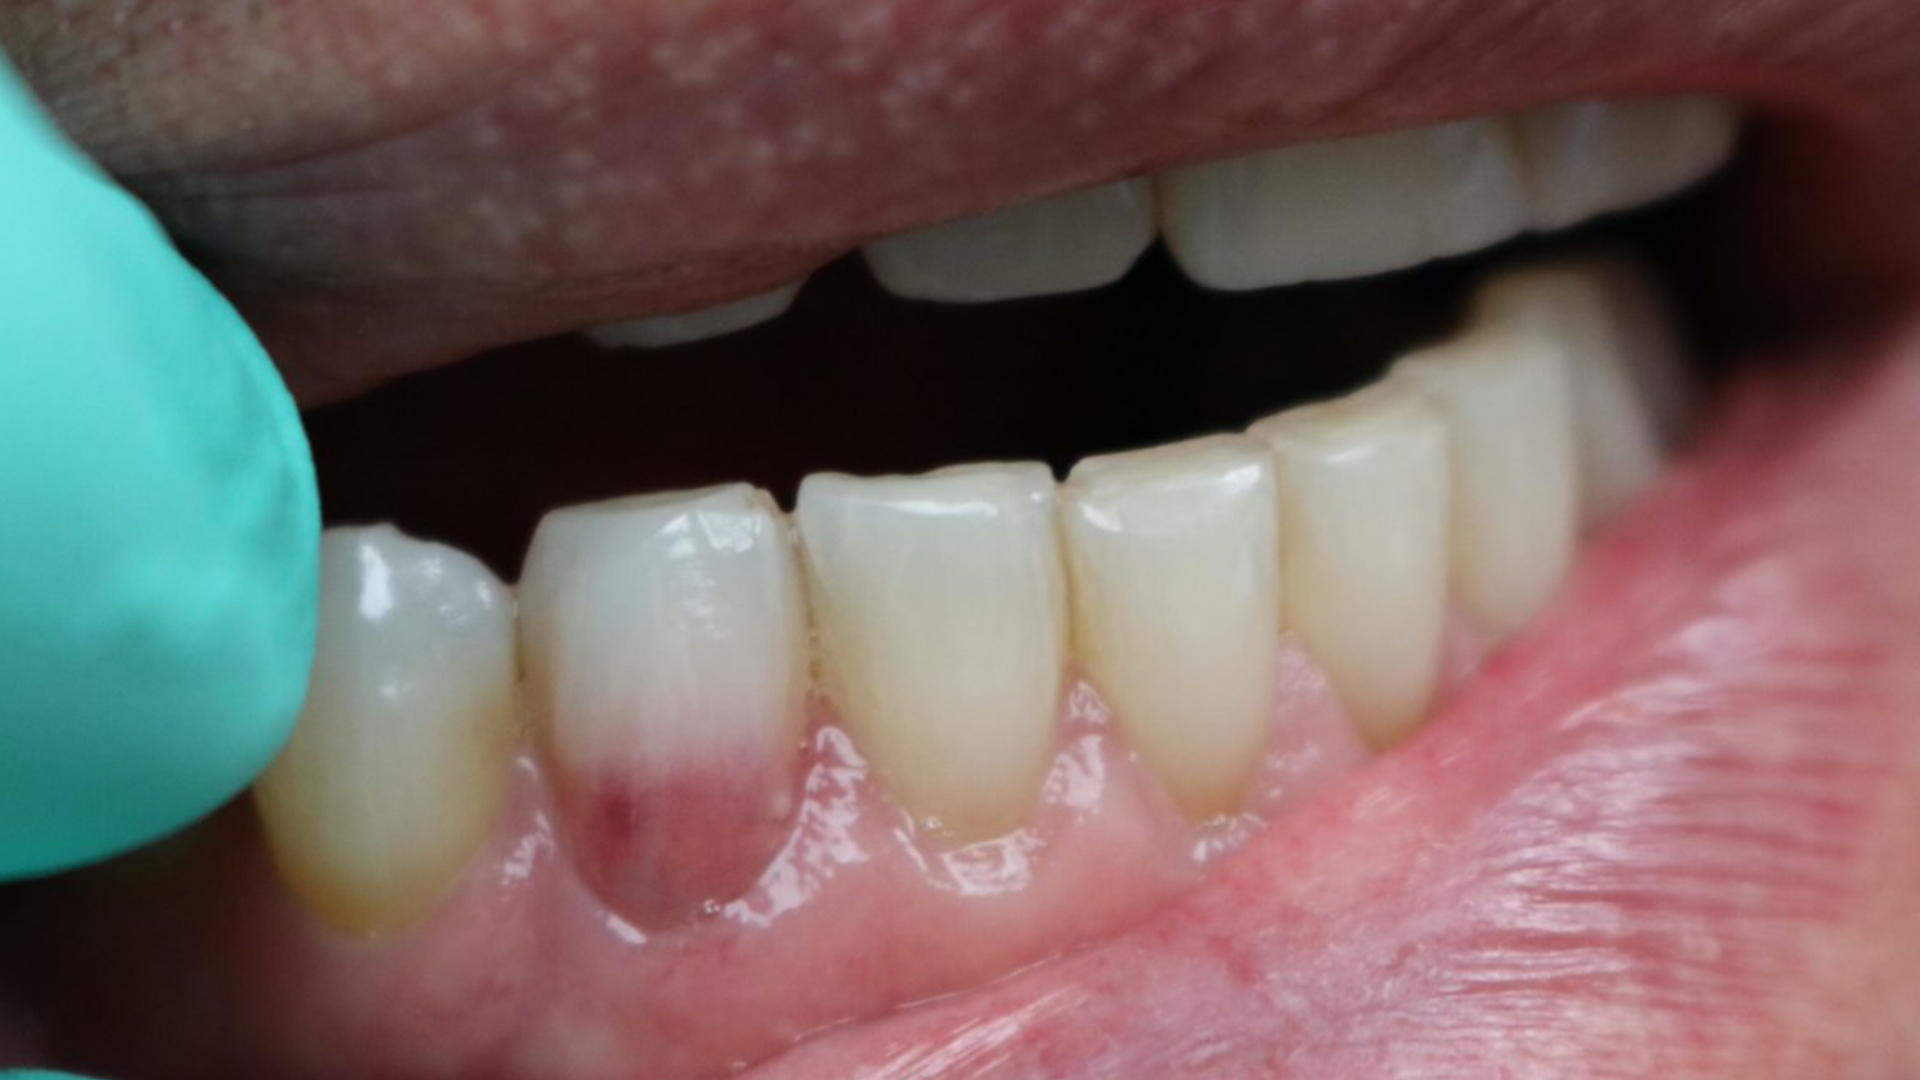

ECR can be differentiated from root caries due to its pink hue and tactile sensation. During the examination, you will find that the dentin surrounding an ECR lesion is usually hard, whereas decay/caries typically feels sticky. When a clinician performs probing around this type of lesion, it will typically bleed—often profusely—because of the highly vascular granulation tissue, a result of the resorptive process.

These pink spots are destructive and often insidious types of lesions that can occur either internally or externally on the tooth, resulting in significant loss of tooth structure. Both lesions have to do with a resorptive process that is occurring—often trauma-induced. When you discover these lesions, you can break down the resorptive processes based on their location: external or internal.

External cervical resorption (ECR) is a type of external resorption that begins at or near the cementoenamel junction. Typically, patients present asymptomatic, and the lesion is simply discovered on routine exams or at prophylactic appointments. This type of resorption can occur in any type of tooth throughout the mouth. Still, a higher percentage of these lesions is noted in the maxillary anterior teeth and the maxillary and mandibular first molars.